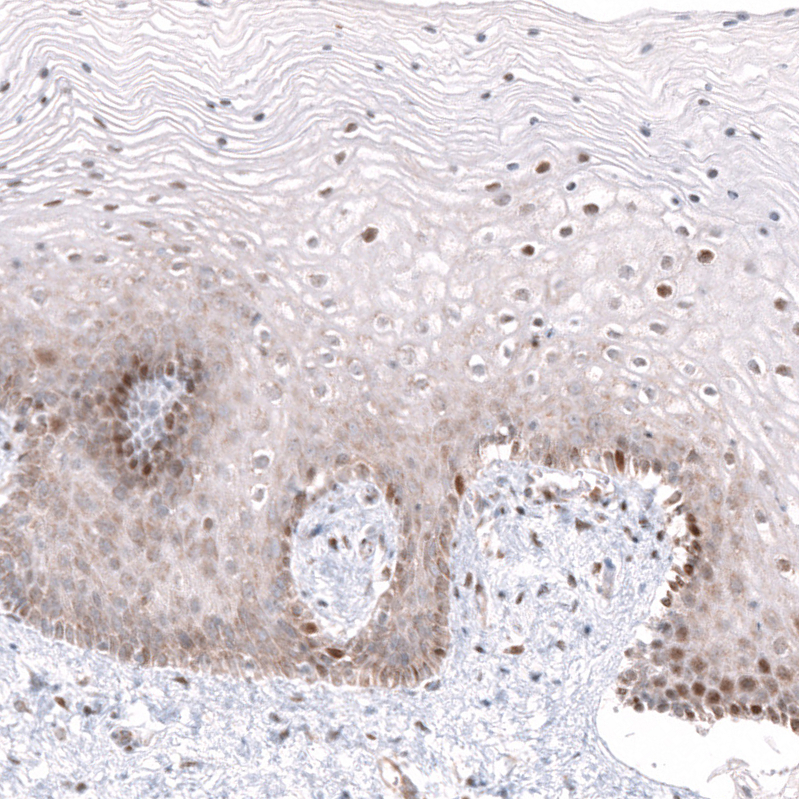

Immunohistochemical staining of human testis shows strong nuclear positivity in cells in seminiferous ducts.